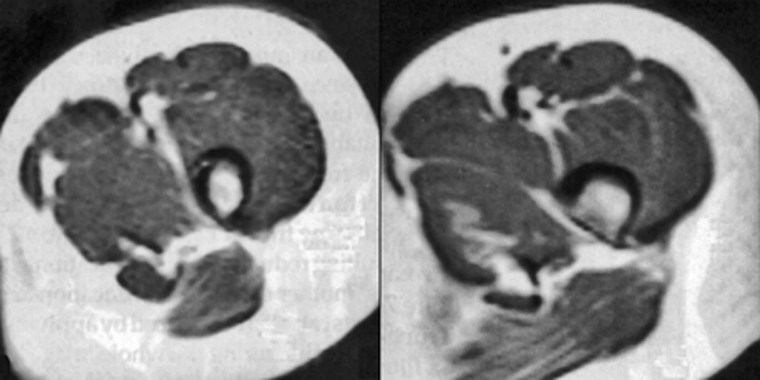

Figura 17-13:

Truncation artifacts.

Top: (a) 60% acquisition with ar­tifacts. (b): 80% acquisition, no artifacts visible.

Bottom: Truncation artifact mimicking sy­ringo-myelia. (c) T1-weighted, (d) T2-weighted im­age.